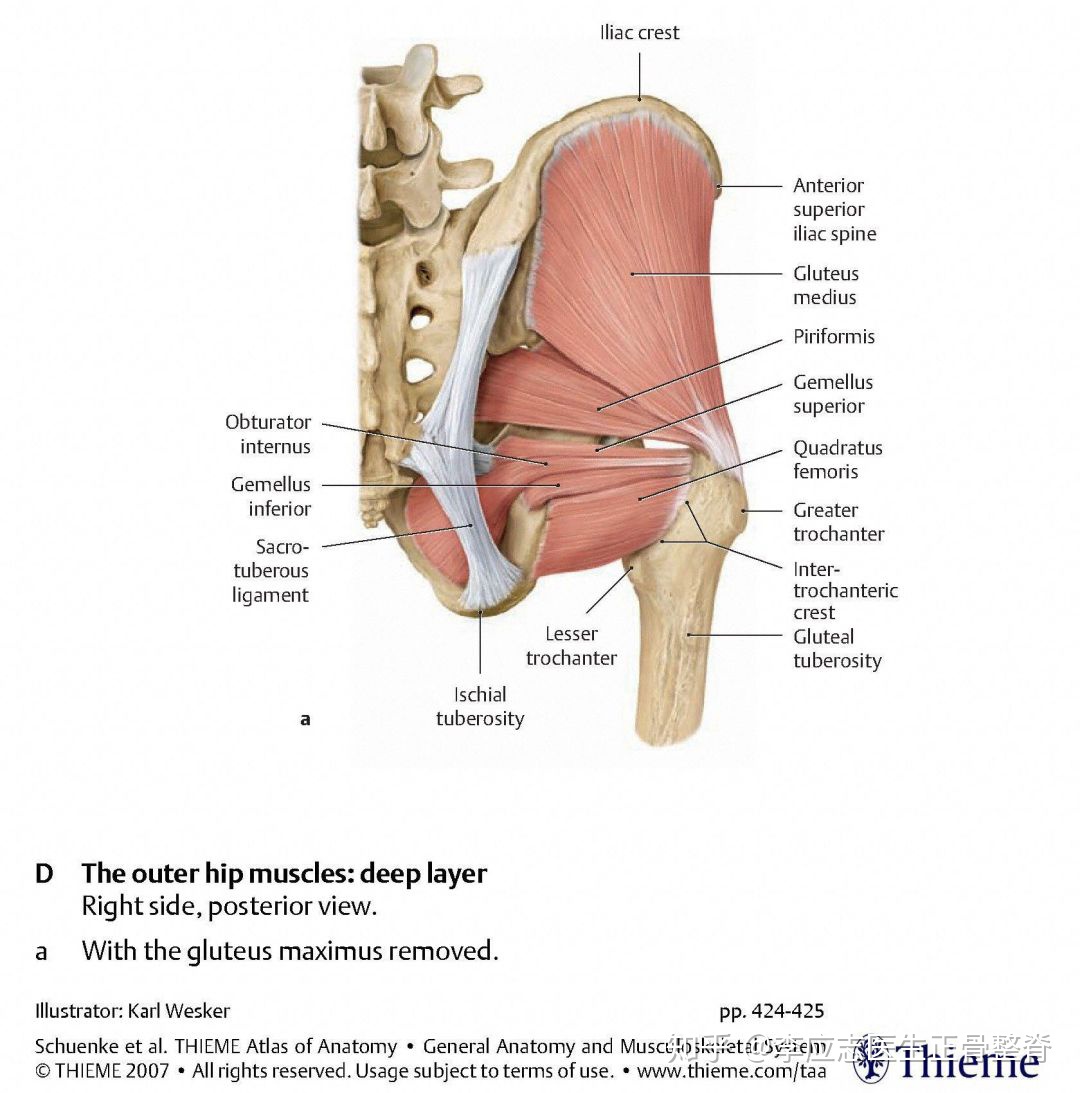

上图中黄颜色的为坐骨神经,很容易受到骶髂关节周围软组织的影响,如果某些组织有炎症或肿胀,刺激该神经,会引起下肢麻木。骶髂关节错位后,臀周的肌肉会痉挛,伴有压痛。

骶髂关节错位后,臀周肌肉,特别是臀中肌易出现痉挛和压痛。